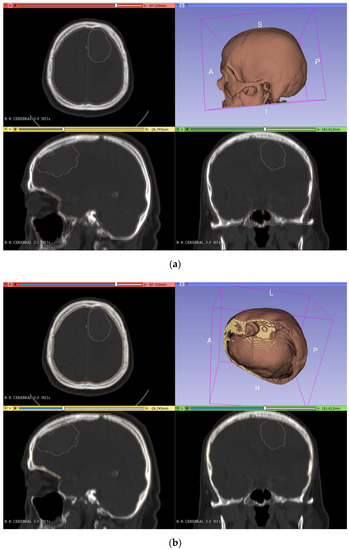

To obtain the final model of the skull, we performed the segmentation (Figure 2a) and cutting (Figure 2b) with the different 3DSlicer tools. For the segmentation step, the ‘threshold’ tool (in the segment editor) was used, adjusting the range values until the selected pixels matched the zone of the bone. After this, the cutting of the lower part of the bone was carried out by using the ‘scissors’ tool. Finally, the resulting model was saved as an STL file and converted into a solid STL file in the Meshmixer software (‘make solid’ tool, in the ‘edit’ menu).

Figure 2.

Segmentation (a) and cutting (b) of the skull model from the DICOM images in 3DSlicer.